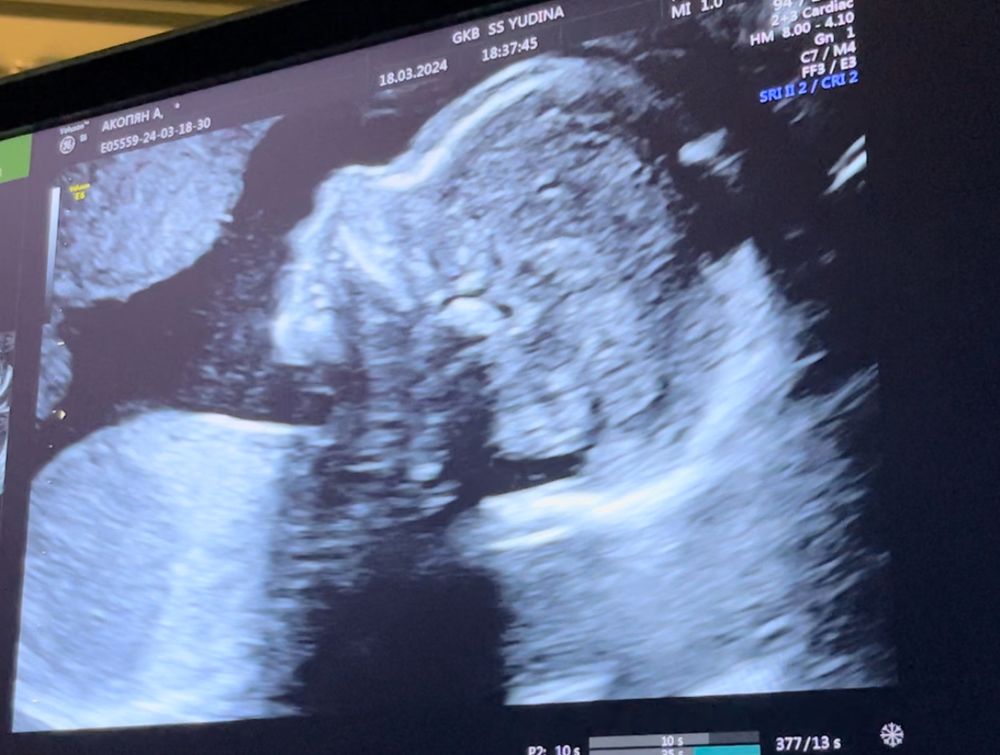

21 неделя беременности в 20 недель сходила на второй скрининг и подтвердили что у нас будет доченька долгожданная дочка🥰♥️💕